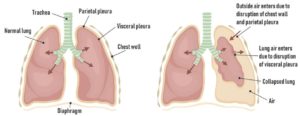

الاسترواح الهوائي أو استرواح الصدر الهوائي يحدث عادة لأسباب عديدة منها أسباب أوليه بدون

وجود أمراض بالرئة أو أسباب ثانوية لوجود مرض بالرئة مثل السدة الرئويه او

الالتهابات أو وجود خراج على الرئة أو أورام بالرئة.

في بعض الأحيان يمكن أن تكون حالة الاستراواح الهوائي على درجة خطورة تهدد الحياة.